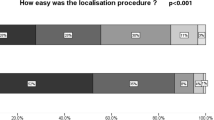

Cost Analysis

The surgery delay rate in the RL cohort was significantly less compared with the WL cohort (0% vs. 10%, respectively; p = 0.029; Table 2). These delays were related to preoperative localisation and were logistical issues because of scheduling of radiology and surgery. The overall cost of RL utilisation over the 2-year study period was AUD$402,281 AUD, which included the cost of each RL use and the reflector. The cost of a single use of RL per case was AUD$3657.10. The average cost of a surgery delay in the WL cohort was AUD$2317.86 due to a mean delay of 79.1 min (SD 50.2). Routine use of RL reduced the surgery delay complication rate by 10% and prevented such delays in 11 cases resulting in a gross cost savings of AUD$25,496.46 (Table 3).

The break-even point analysis demonstrated that 290 cases using RL are needed to be performed routinely to recover costs of the medical device based on the average surgery delay cost of AUD$2317.86 and a surgery delay reduction rate of 10%. The greater the number of cases performed with RL, the greater the potential savings when this break-even point is overcome. Baseline cost-utility analysis showed that although the cost of WLE with RL was greater than that with WL by AUD$566.92, use of RL yielded a greater clinical benefit of 1.15 QALYs and the ICUR was only AUD$492.97 (Table 4). The one-way sensitivity analysis demonstrated that using RL was more cost-effective when the surgery delay complication rate with WL was ≥10% (using a maximum willingness to pay of AUD$50,000 per QALY).